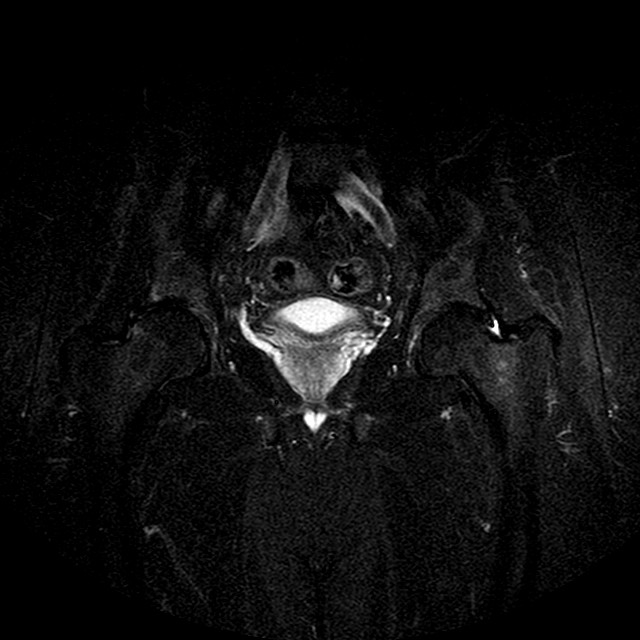

STIR

Evidenti e simmetriche alterazioni osteofitosiche in regione coxo femorale con riduzione delle rime articolari. Degenerazione completa del cercine glenoideo. Non attuali segni di versamento articolare. Non segni di edema osseo che escludono attuale algodistrofia od osteonecrosi. Lieve e simmetrica riduzione del trofismo della muscolatura glutea.